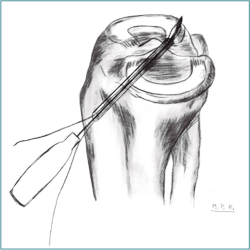

• Técnicas in situ: son las más frecuentemente utilizadas para la reinserción de las raíces anteriores; se coloca un implante directamente en la zona de inserción anatómica sobre el cual se reinserta la raíz meniscal, que debe ser previamente cruentada, preparándose un lecho para la inserción del implante (Figura 9). Se realiza el paso de las suturas a través de la raíz meniscal con gancho de sutura, pasador de sutura directo/indirecto o con ayuda de una aguja de espinal con un hilo monofilamento insertado para traccionar del hilo del anclaje (Figura 10). Las ventajas teóricas de esta técnica son que evita la realización de túneles tibiales que podrían interferir con los túneles de reconstrucción del LCA y que evita la necesidad de una fijación adicional en la cortical anterior tibial(60); no obstante, existe la posibilidad de que falle el sistema de anclaje y técnicamente son más demandantes(48). La fijación artroscópica de las raíces meniscales con el uso de anclajes fue descrita originalmente por Engelsohn en las raíces posteriores con el uso de un portal accesorio posteromedial(71).

Figura 9. Imágenes artroscópicas de la colocación de un anclaje para la reinserción de la raíz anterior del menisco lateral. A: colocación del anclaje; B: hilos del anclaje colocado en la zona de inserción previamente cruentada.

Figura 10. Imagen artroscópica del paso del hilo monofilamento insertado en una aguja espinal perforando la raíz anterior del menisco lateral en el que se enlazará el hilo del anclaje y traccionar del mismo para la reinserción de dicha raíz.